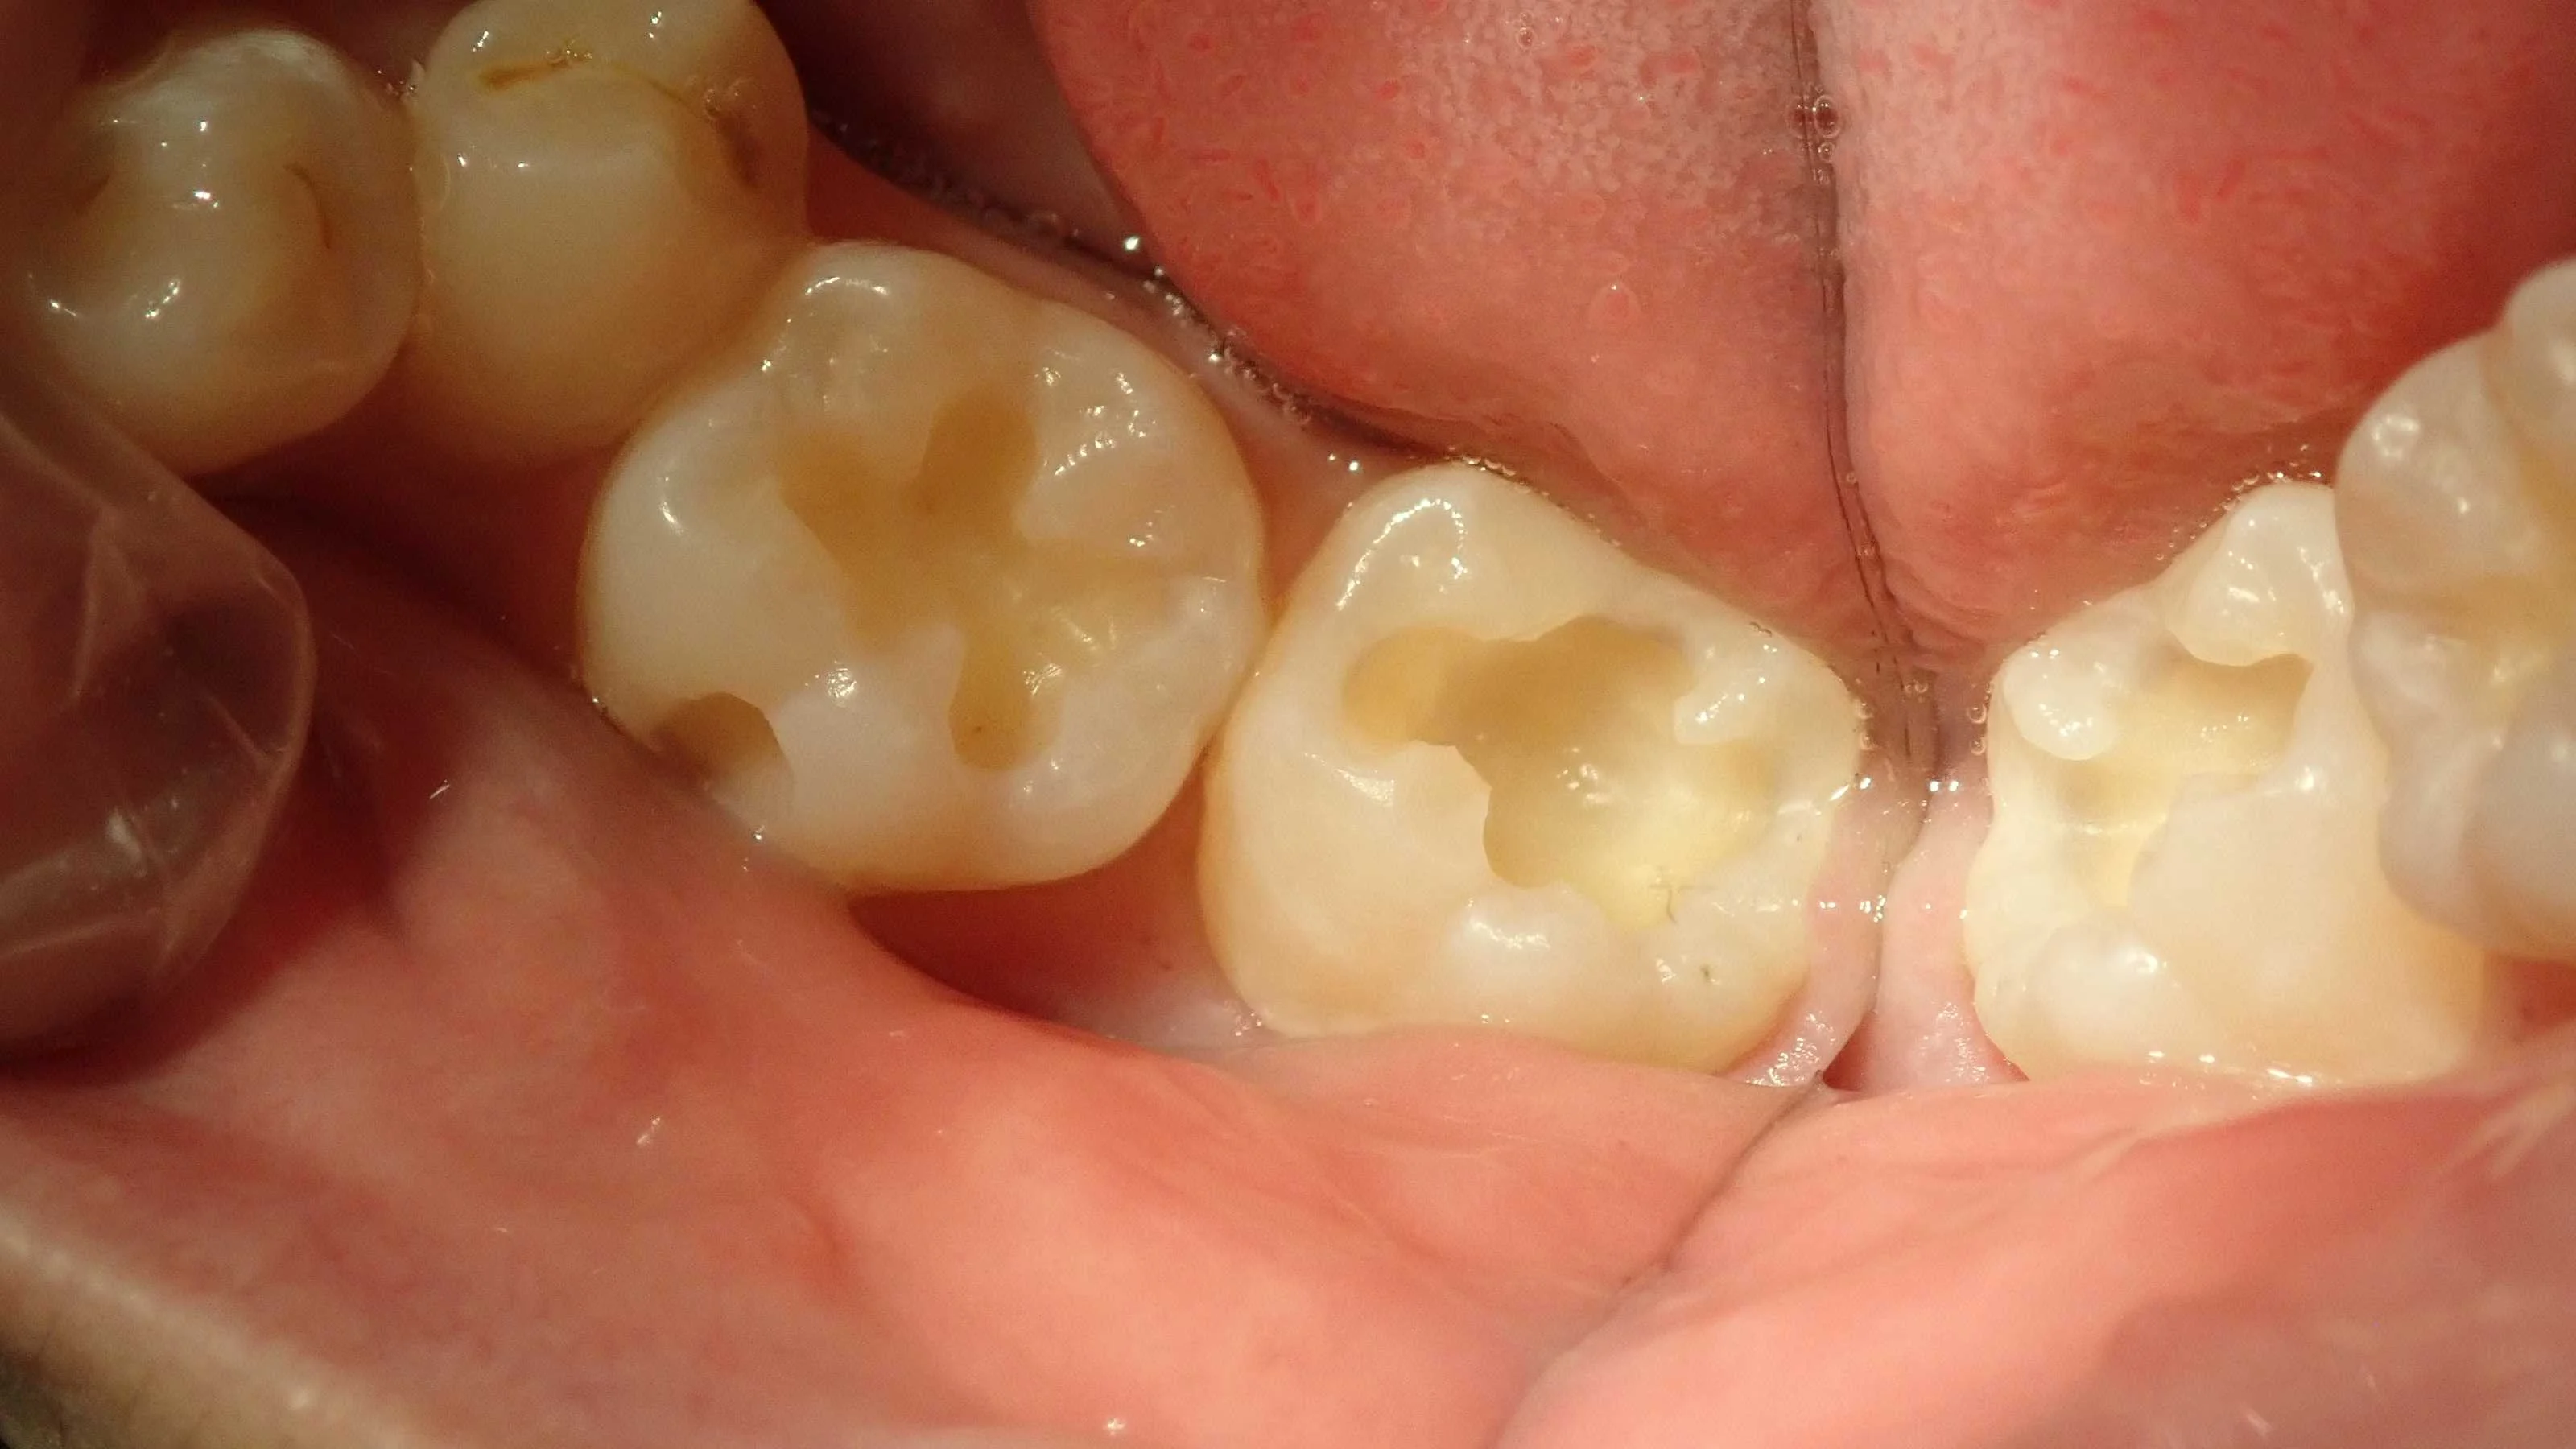

で、虫歯を取り切った写真がこちらです。

ごめんなさい。奥の光の反射が激しくてどれだけ深いのかはわかりづらいですね。

「神経まではいかないまでも、かなり大きい」

といった感じでした。

ただ、今回は歯と歯の間には虫歯がなかったので、強度的には問題がないと判断し、説明した上でそのままコンポジットレジンでの治療となりました。